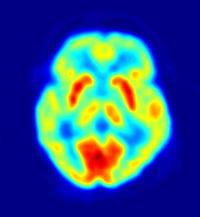

وتمكن تقنيتان جديدتان مأمونتان هما: التصوير المقطعي المغناطيسي بابتعاث البوزيترونات والتصوير بالرنين المغنطيسي الوظيفي، العلماء من دراسة الدماغ السليم أثناء عمله. ولاتتطلب هاتان التقنيتان اتصالاً مباشرًا بالدماغ، ولكنهما ينتجان صورًا شبيهة بصور الأشعة السينية، والتي توضح أي أجزاء الدماغ يعمل أثناء أداء الشخص نشاطًا ذهنيًا أو بدنيًا، حيث يوضح التصوير المقطعي بابتعاث البوزيترونات أجزاء الدماغ الأكثر استهلاكًا للجلوكوز، بينما يوضح التصوير بالرنين المغنطيسي الوظيفي، الأجزاء التي يشير فيها استهلاك معدلات عالية من الأكسجين إلى نشاط الجزء.